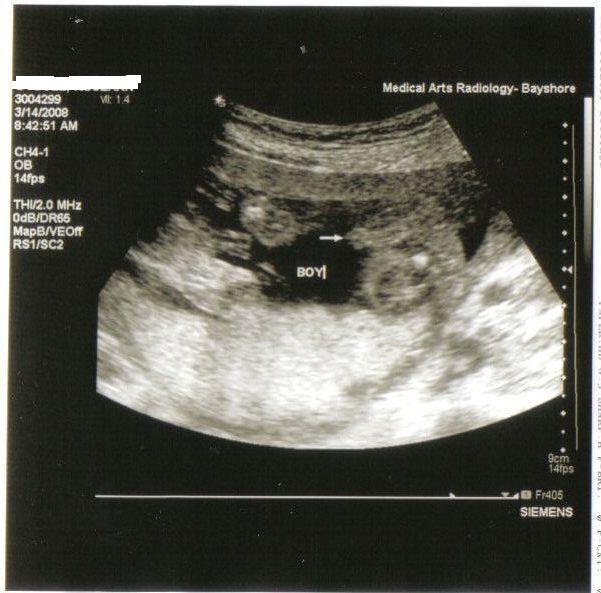

This is mine but you can clearly see his boy parts Image Attachment(s):

WOW...they said Boy at my 12 week sono and it wasn't as pronounced as that!!! Now I'm wondering if he was wrong

I was told by my doctor that a white dot usually means a girl on an early sono....boy parts will look like the big picture above.....also it all depends on the position of the baby and the shot so don't stress if you didn't really see anything........